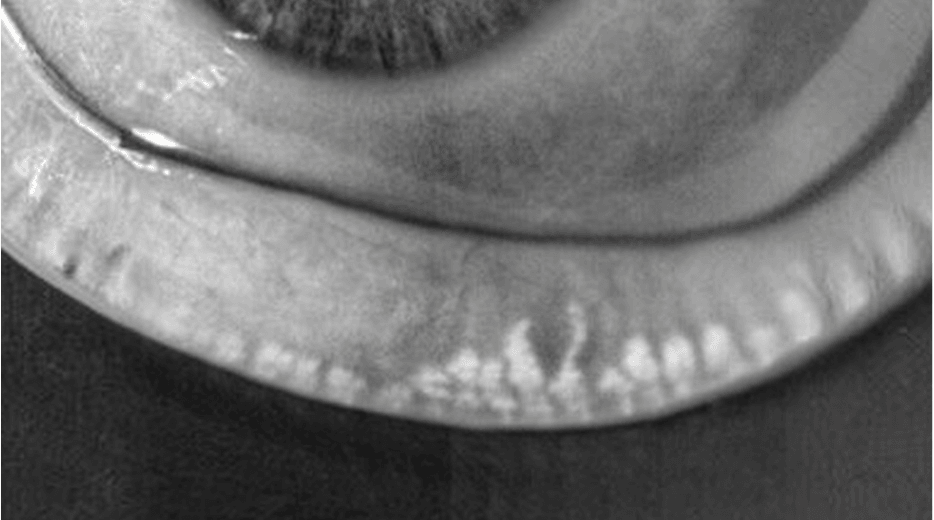

Meibomian Gland Dysfunction (MGD) Assessment

Meibomian Gland Dysfunction (MGD) can be

thoroughly assessed through precision diagnostics

MGD is a chronic, progressive,

and obstructive condition.

Maintaining the healthy function and structure of the meibomian glands

before dry eye symptoms appear is crucial.